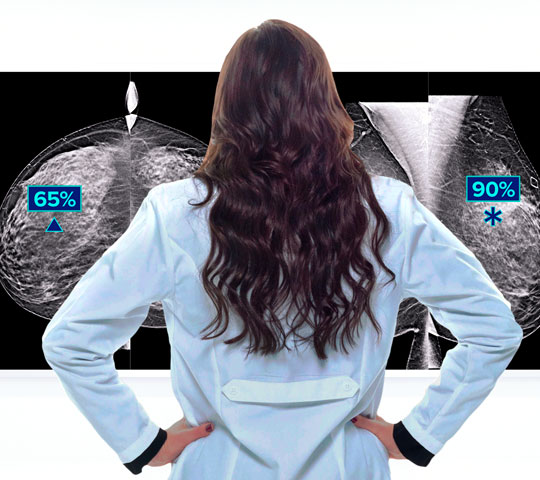

Hologic is transforming breast care. We apply cutting-edge science to accelerate discovery, improve efficiency and continually sharpen precision.

Time is precious when it comes to effective detection, diagnosis and treatment of breast cancer. We strive to save you time at every step along the Breast Health Continuum of Care to help more women have more time in better health.